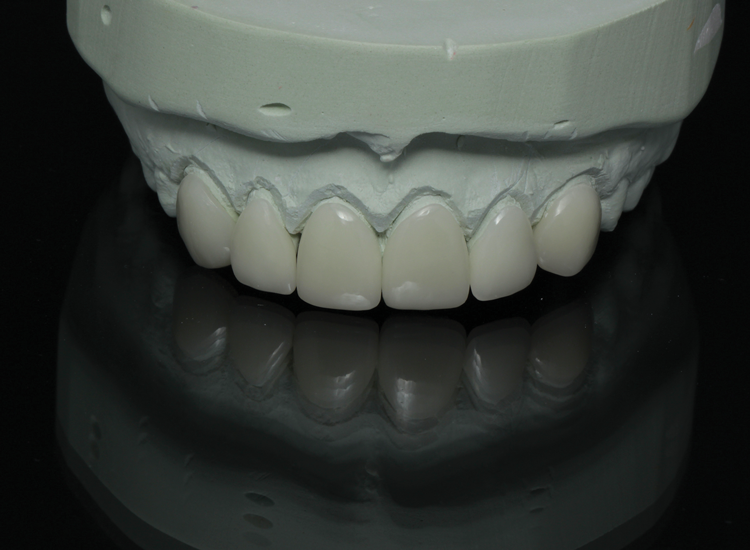

(3.) Facial, incisal, and intaglio views of the composite veneers that were designed and milled for teeth Nos. 6 through 11.

Figure 3

(4.) Facial, incisal, and intaglio views of the composite veneers that were designed and milled for teeth Nos. 6 through 11.

Figure 4

(5.) Facial, incisal, and intaglio views of the composite veneers that were designed and milled for teeth Nos. 6 through 11.

Figure 5